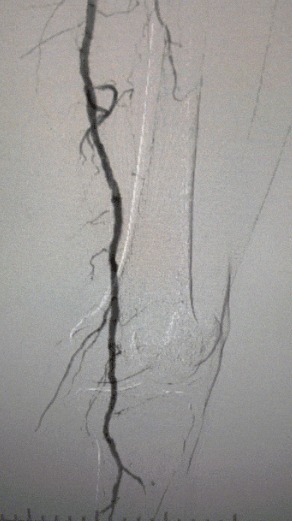

· Pencitraan preoperatif: menyebarkan stenosis parah, menyebarkan kalfikasi dalam jalan setapak anggota bawah bilateral

Prosedur pasca, stenosis arteri meningkat secara signifikan, aliran darah meningkat, dan suhu kulit mawar. Tidak ada terjadi komplikasi setelah operasi. Baik pasien maupun tim bedah sangat puas dengan hasilnya.

Kasus ini menyorot terobosan besar dalam pengobatan invasif minimal untuk arteriev anggota tubuh bawah parah, memberikan solusi yang lebih efektif untuk kasus yang menantang.